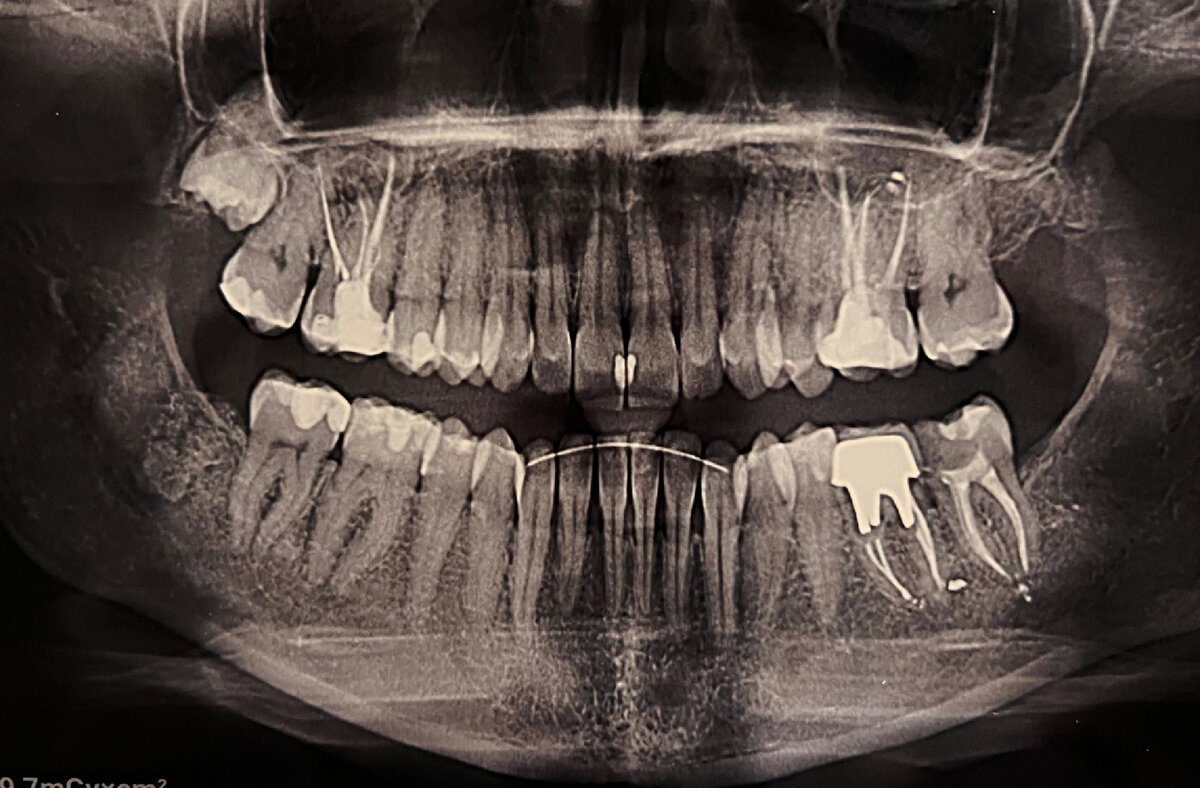

Скооолько я созревала….. исчисляется уже в годах. И вот наконец-то дошла. Предварительно сделала панорамный снимок, чтобы наш разговор с доктором был более информативный и предметный.

Я вот когда на руки получила панорамный снимок, первым делом начала выискивать свои кисты в районе верхних 6-к. Их в свое время обнаружили на КТ верхней челюсти. Не видно, я вообще не считаю ОРТО сильно информативным снимком. Ну так, посмотреть расположение корней, понять какие «живые» или как там по стоматологически- витальные и интактные (🤓не зря же я достаю стоматологов своими вопросами). А вот какие-то хронические моменты не всегда можно разглядеть.

Так вот я так уперлась в поиск этих кист, что даже не обратила внимание на проблему на нижнем фронте((( рецессия сильнее, чем мне хотелось думать. А думать я вообще об этом не хочу, потому что боюсь

Вот как раз под ретейнером видно снижение уровня кости